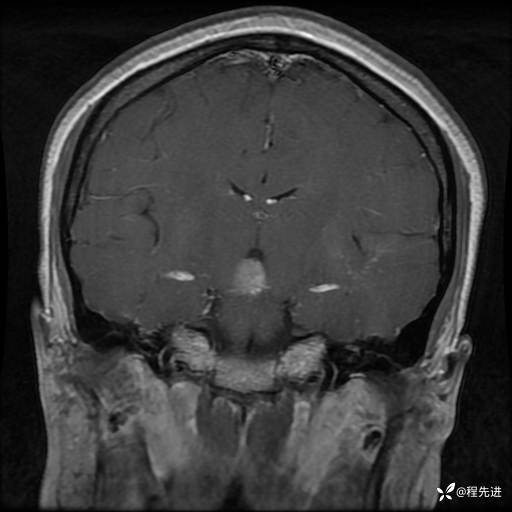

MRI平扫+增强:

T2:

T1+C: